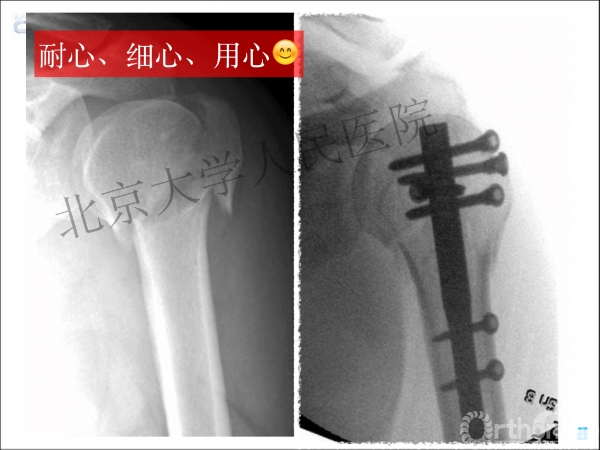

内侧皮质粉碎,低位外科颈骨折,肱骨头-干角维持困难。

术后复位丢失,肱骨头内翻畸形。

能否该偏心固定(钢板)为髓内固定,增加力臂?

早知今日,何必当初?

此时对比髓内钉是不是有很大优势?